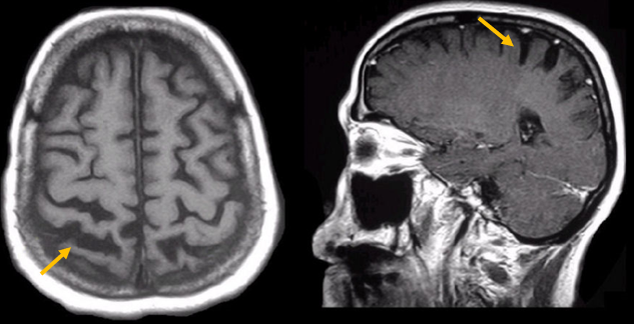

피질 기저핵 변성은 비대칭 증상을 두드러지게 보인다는 점에서 파킨슨병과 비슷합니다. 그러나 파킨슨병과 비교해 보았을 때 양측의 차이가 아주 심하게 나타난다는 특징이 있습니다. 질병 초기에 한쪽 손으로 동작을 하거나 계획된 행동을 하는 기능이 현저하게 떨어집니다. 간단한 손가락 모양도 따라 하지 못하는 현상을 보입니다. 또한 의지와 상관없이 제멋대로 움직이는 통제불능 손이 나타날 수 있습니다. 체위 떨림, 경축, 운동 완만과 같은 파킨슨병에서 볼 수 있는 증상들은 피질 기저핵 변성에서도 관찰될 수 있습니다. 또한 집중력 장애, 수행 장애, 이름 대기나 언어의 유창성이 떨어지는 등 전두엽 및 두정엽과 관련된 인지 장애가 나타납니다. 피질 기저핵 변성은 뇌 자기공명영상(MRI)에서 증상의 반대쪽 전두두정엽의 위축 소견이 특징적으로 나타납니다. 뇌포도당 양전자 단층촬영(PET)에서도 전두엽, 뇌기저핵에 비대칭적인 대사 저하의 소견이 보입니다.

[피질기저핵 변성 환자의 뇌자기공명영상에서 확인되는 비대칭 뇌피질의 소견]